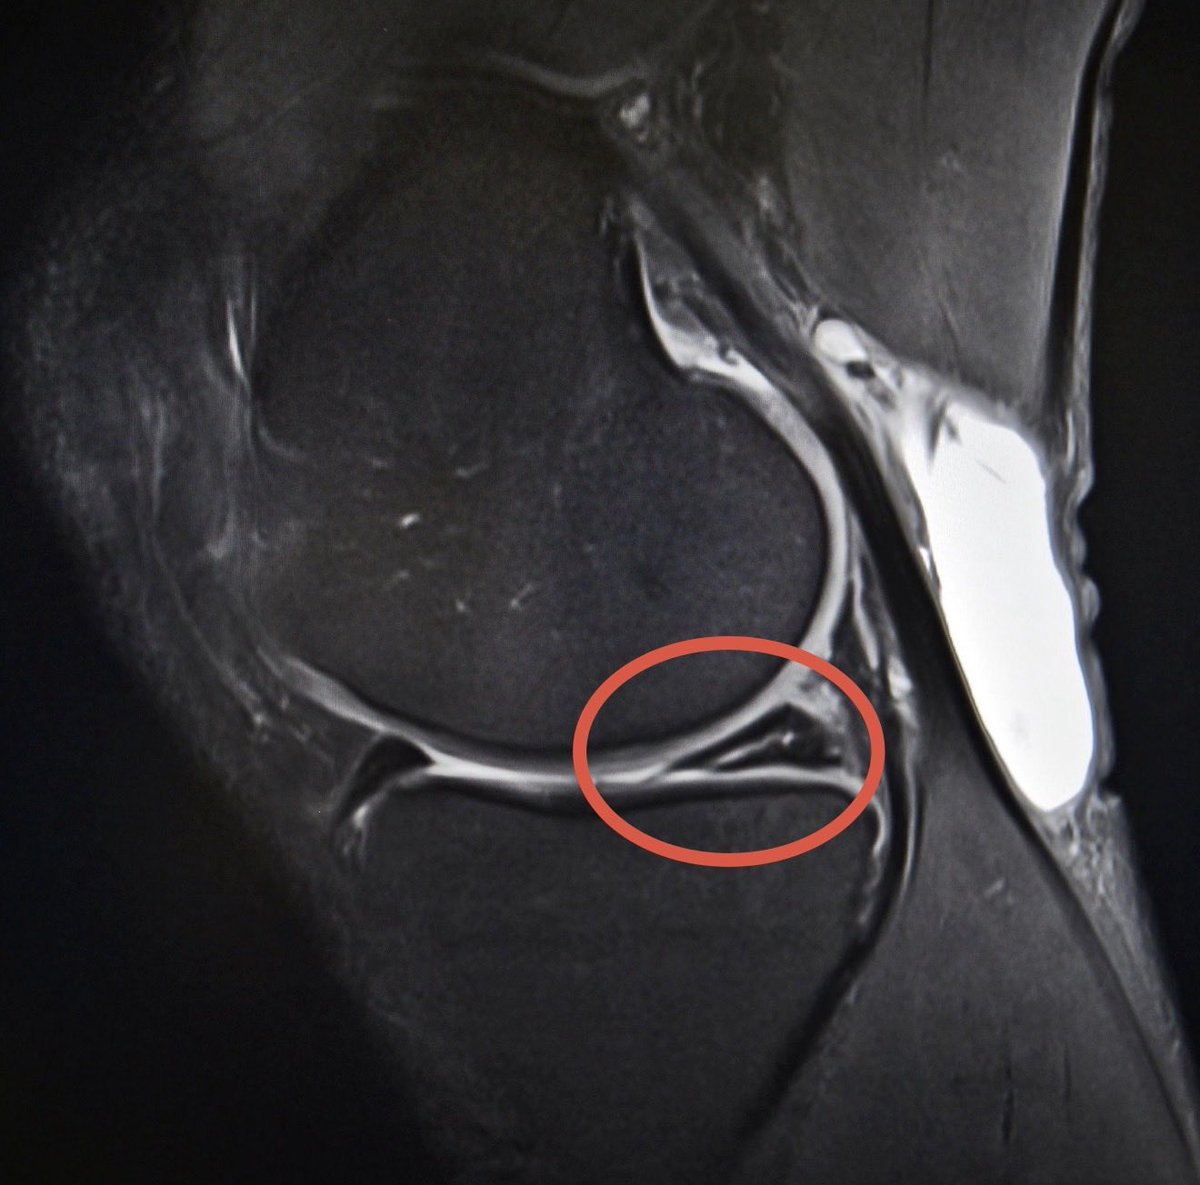

Maxx Crosby is eight weeks from having meniscus surgery and got off crutches only last week. He is on schedule, and they are working to get him ready for the regular-season opener. Here is what Crosby’s knee surgeon, Dr. Neal ElAttrache, said to ESPN this morning: “Maxx Crosby is doing very well in the early part of his rehab and recovery from surgery to treat a significant meniscus tear and the related stress injury to the bone and cartilage in his knee. He is certainly on track in his planned program….he feels very well and is already much improved compared to before surgery. “We truly respect the work of the Ravens staff with Maxx regarding the contract physical exam. We also understand the challenge the staff faces when tasked to provide a future risk assessment based on an evaluation early in the recovery process. This is especially challenging when dealing with an elite player like Maxx considering the level of commitment necessary for a team to obtain him. The timing of this assessment is unfortunate because the apparent risk will lessen as his recovery progresses and his return to performance over the next few months becomes clear. “At this point, Max is doing an excellent job attacking his rehab and his knee is responding very well. We look forward to Maxx returning to his elite level of performance this season as planned and for several more to come.”